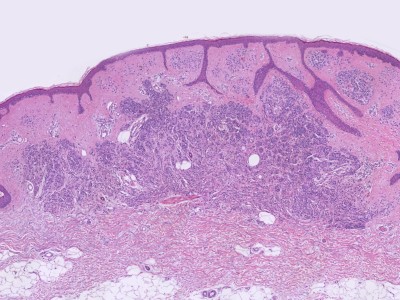

Histologische

variantenDe naevi naevocellularis worden ingedeeld in 3 histologische

varianten

-

junctional naevus (naevus naevocellularis

marginalis): opeenhoping van naevuscellen in de epidermis

dermal

/

intradermal naevus (naevus naevocellularis dermalis):

opeenhoping van naevuscellen in de dermis

compound naevus

(naevus naevocellularis epidermo-dermalis): opeenhoping van naevuscellen in

zowel dermis als epidermis

Zie ook de ingescande PA-coupes (

compound

naevus) van de

afdeling

pathologie van de University of Toronto.